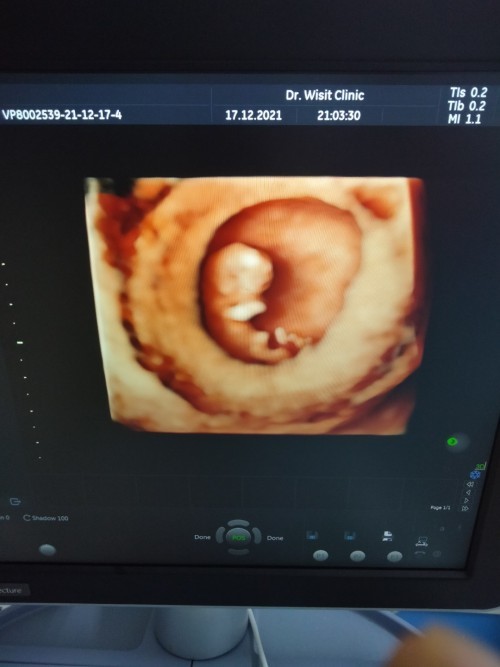

เค้าก็10วีคจ้า 😍

บ้านนี้ 10w1d 3.41 cm คะ